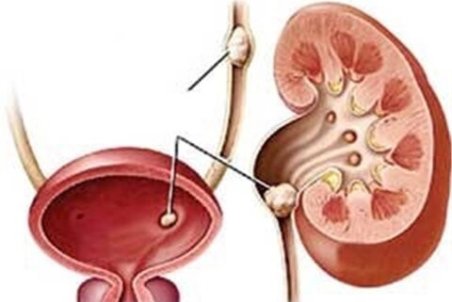

علت ابتلا به سنگ مثانه چیست؟

سنگ مثانه که اغلب ناشی از عدم توانایی کامل مثانه بوده، ممکن است خود را به طور ناگهانی و همراه با درد شدید شکم و وجود خون در ادرار نشان دهد.